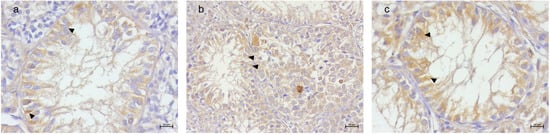

3.2. Immunohistochemical Results